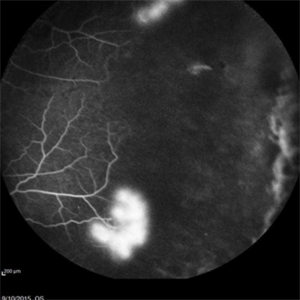

Angiography showed normal vessels posteriorly but severe capillary drop out throughout the periphery OU with scattered severe neovascularization at the edge of the capillary drop out peripherally.

Sickle Cell Retinopathy Sickle Cell RetinopathySep 13 2015 by Thomas A. Ciulla, MD, MBA, FASRS Angiography showed normal vessels posteriorly but severe capillary drop out throughout the periphery OU with scattered severe neovascularization at the edge of the capillary drop out peripherally. Photographer: Thomas Steele Condition/keywords: peripheral retinal neovascularization, sea fan, sickle cell retinopathy